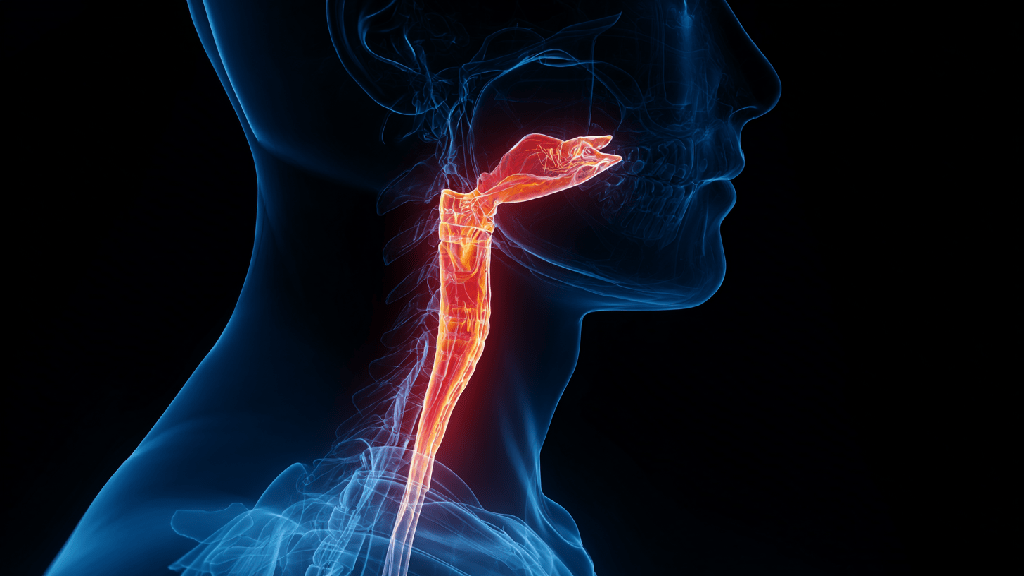

Ахалазия кардии пищевода — это заболевание, при котором нарушается координированная перистальтика (движение) пищевода, не происходит адекватного расслабления кардиального сфинктера. Слово «ахалазия» происходит от греческого a — «отсутствие», chalasis — «расслабление», что в точности описывает суть патологии.

Нижний пищеводный сфинктер (кардиальный отдел) в норме должен расслабляться при глотании, чтобы пища беспрепятственно попадала в желудок. При ахалазии эта функция нарушается — сфинктер остается в сокращенном состоянии. Из-за этого пища скапливается в пищеводе, вызывая его растяжение, воспаление, повреждение слизистой.